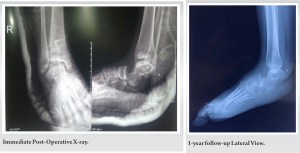

After the surgery, a below-knee splint was applied for 3 months, and the patient was advised non-weight-bearing ambulation. Sutures were removed at 2 weeks, and then three cycles of adjuvant chemotherapy were given. At 3 months of follow-up, partial weight bearing was allowed with elbow crutches and an ankle-foot orthosis. The patient was followed up every 6 weeks. At a 1-year follow-up, a customized silicon heel cup and shoes were given for full weight-bearing ambulation. At the end of 1 year, a PET-CT revealed no evidence of metabolically active disease.

In this case, the patient was treated with a combination of chemotherapy and limb salvage surgery. Neoadjuvant chemotherapy is used to reduce the size of the tumor before surgery and to prevent micrometastasis. The patient underwent a wide en bloc resection of the calcaneum and received adjuvant chemotherapy after the surgery. The patient was followed up for 1 year and had no recurrence of tumor. She was able to bear weight fully with a customized heel cup.